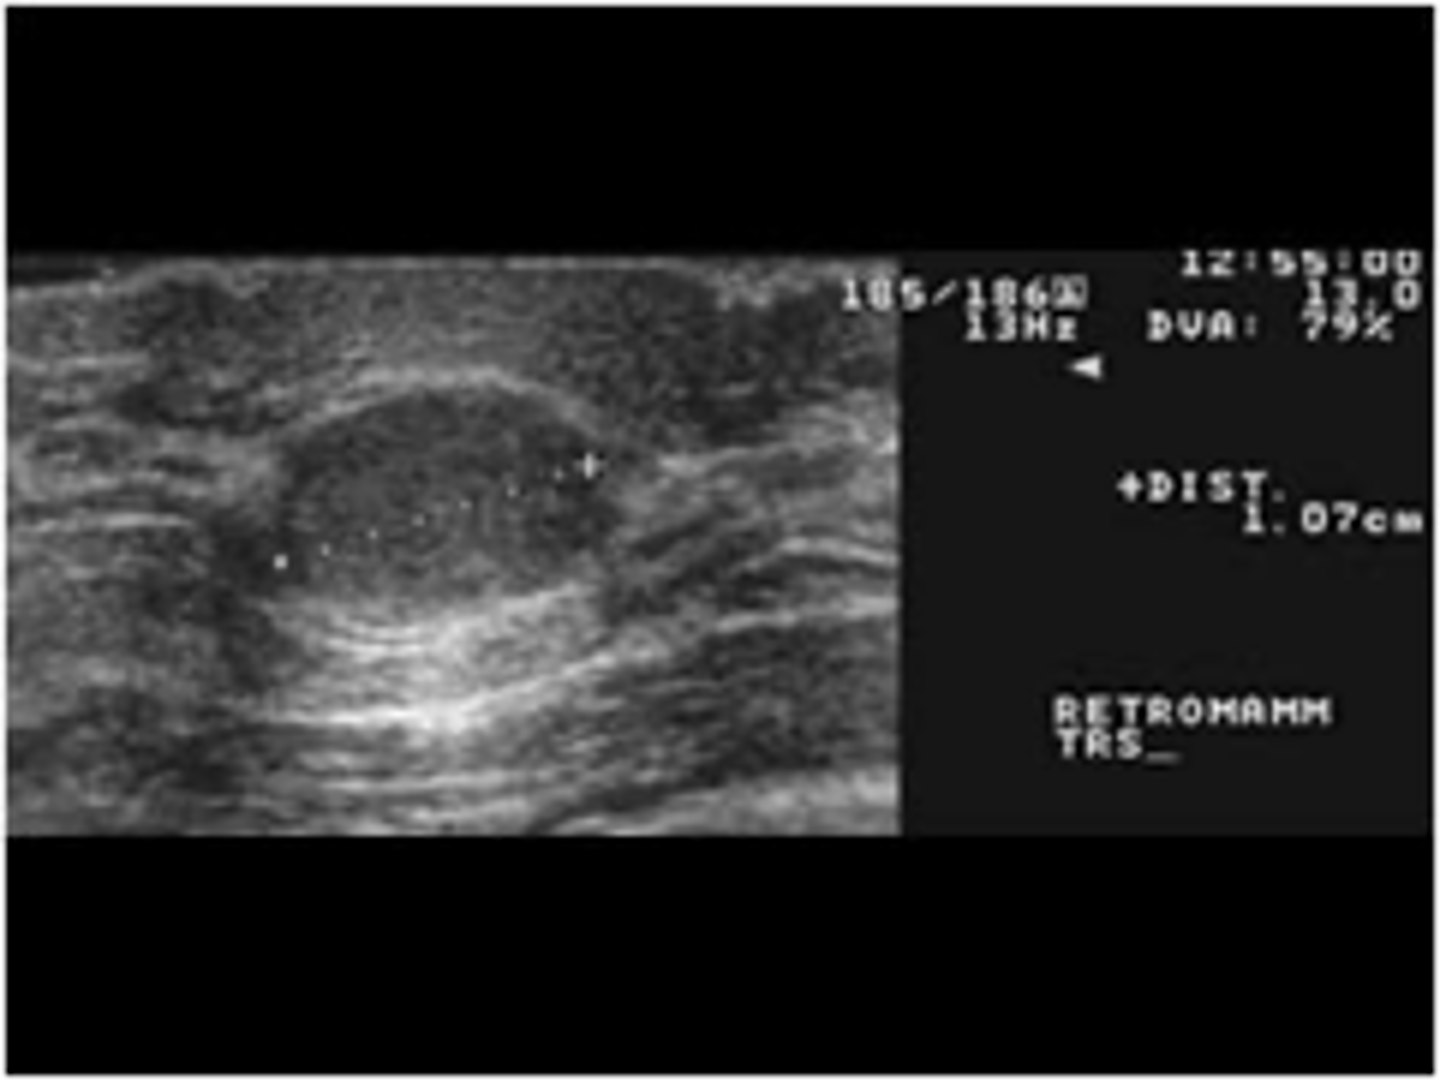

cyst

30-50 yo

Regress after menopause

Single or multiple

Round

Soft/firm, rubbery

Well -demarcated

Mobile

Often tender